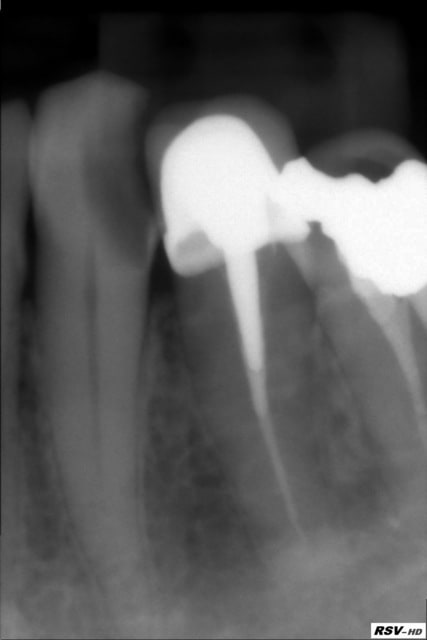

Tout est dit, par la patiente qui vient pour une endo 33 ce matin, après devis. La dent est peu symptomatique et elle ne veut pas mettre une couronne (car 215€ en charge) et elle ne veut pas non plus mettre une provisoire (payante pour le coup) en attendant 6-7 mois pour changer de mutuelle (soi-disant).

Elle préfère ne pas faire l'endo, car je ne peux pas lui assurer le parfait état de la face vestibulaire de la 33 (en hauteur et en largeur bien évidemment) après l'endo. Je l'ai prévenue du risque de pulpite, elle sait mais elle verra quand elle sera au pied du mur...

C'est dommage. La 34 est en train de se mésialer et de s'engager dans la 33. Pour le coup faire de l'esthétique dans ces conditions ça ne va pas être facile. Mais bon, si elle ne veut pas, tu vas pas la forcer. Ce sont ses dents, pas les tiennes.